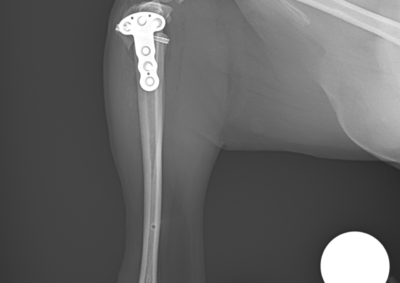

注意 ボタンをクリックした先に、治療中および手術中の画像が説明で使用されている場合がございます。 そのような画像に弱い方は閲覧なさらないようお願いいたします。 整形外科 若齢犬の橈骨固定術 #271 整形外科 前十字靭帯断裂(中型犬)に対するCBLO #255 整形外科 超小型犬に対する上腕骨遠位Y字骨折 整形外科 大型犬の前十字靭帯疾患(慢性経過)に対するCBLO #254 整形外科 橈骨固定術 #270 整形外科 膝蓋骨内方脱臼に対する人工滑車置換術 PGR #23 整形外科 犬の前十字靭帯(疾患)部分断裂に対するCBLO #253 整形外科 犬の前十字靭帯断裂に対するCBLO #252 整形外科 膝蓋骨内方脱臼+前十字靭帯断裂に対するPGR#22・LSS 整形外科 大腿骨骨折 整形外科 橈骨固定術 #269 整形外科 上腕骨外顆骨折の癒合不全 123456> 症例カテゴリー 放射線治療整形外科軟部組織外科脳神経外科内科腫瘍外科救急・集中治療リハビリテーション科腫瘍内科内視鏡科脳神経科呼吸器外科中医・漢方猫の腎移植循環器科